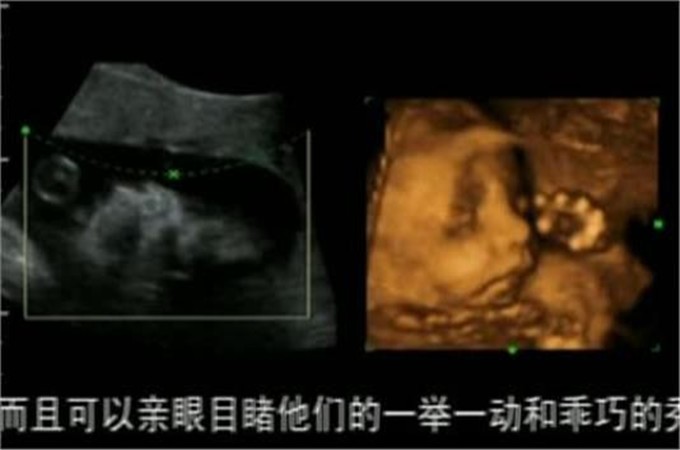

大概在五个月的时候,在老公的陪同下张女士去做了产检,通过仪器的照片可以看到宝宝的样子,没想到让张女士感到很尴尬,四维照下的宝宝原型毕露,和自己想象的完全不一样。宝宝的鼻子和嘴比较平而且还很小,最关键的是头像看起来不太标准,至于长的像谁看不出来,不过可以肯定的一点是有点丑。

四维照给人感觉和现实不太一样,感觉一点都不真实,只能看到大概的轮廓,而且也是隐隐约约的,张女士本来以为可以看到一个帅气的宝宝,哪怕是稍微可爱一点也可以,结果一点都没让自己满意。反正孩子现在还在发育中,相信将来孩子出生的时候一定不会让自己失望的。

角度不一样的时候看到的结果也不同,这是因为四维照从不同的角度把他们合成之后,你才能看到眼前的结果,有时候看到的结果确实是最丑的角度,只能看到一个大概的样子,另外宝宝的环境是在羊水中,也会显得样子模糊。